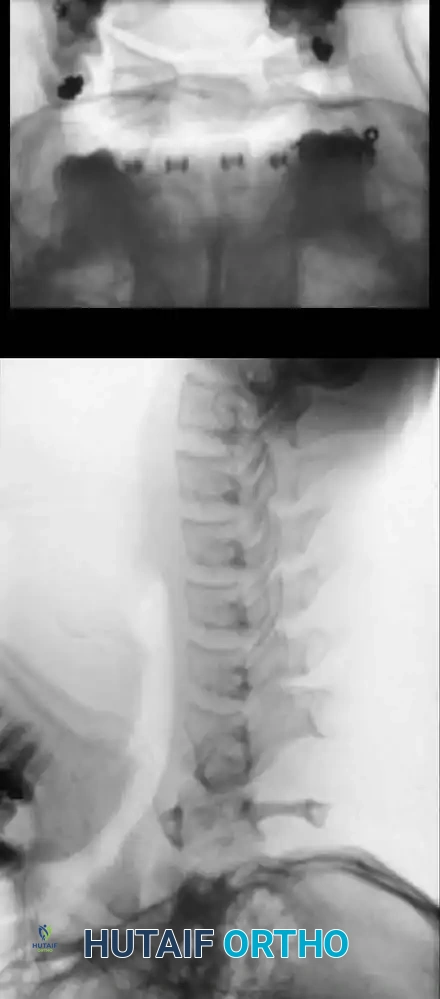

Routine cervical spine radiography, including an open-mouth odontoid view, is the first line of investigation.

Image

Fig. 37-4 Lateral radiograph (A) and open-mouth odontoid radiograph (B) showing os odontoideum.

• Aplasia: Appears as a slight depression between the superior articulating facets on the open-mouth view.

• Os Odontoideum: A distinct space is visible between the C2 body and the free ossicle. The ossicle is typically half the size of a normal dens, with smooth, sclerotic borders. This must be differentiated from an acute Type II odontoid fracture, which presents with a thin, irregular, non-sclerotic radiolucent line.